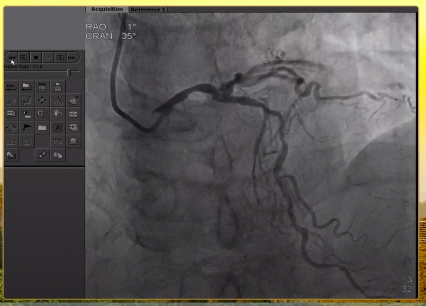

造影结果

左主干偏心斑块,重度狭窄;前降支中段重度狭窄;回旋支开口扭曲伴重度狭窄,支架远端完全闭塞,高位钝缘支开口重度狭窄;右冠开口次全闭塞,开口处可见支架影,中段支架远端完全闭塞。

右冠造影结果